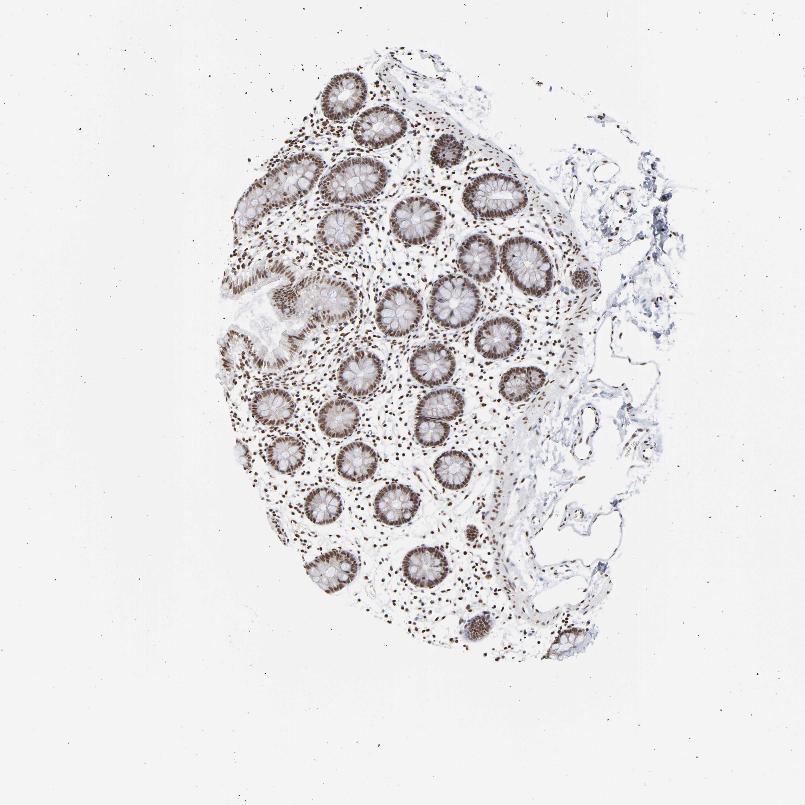

COLON - Antibody stainingi

Antibody staining in the annotated cell types in the current human tissue is reported as not detected, low, medium, or high, based on conventional immunohistochemistry profiling in selected tissues. This score is based on the combination of the staining intensity and fraction of stained cells.

Each image is clickable and will lead to virtual microscopy that enables deeper exploration of all samples and also displays staining intensity scores, fraction scores and subcellular localization as well as patient and tissue information for each sample.

Antibody HPA019150Antibody CAB003803

Endothelial cells HighHigh

Glandular cells HighHigh